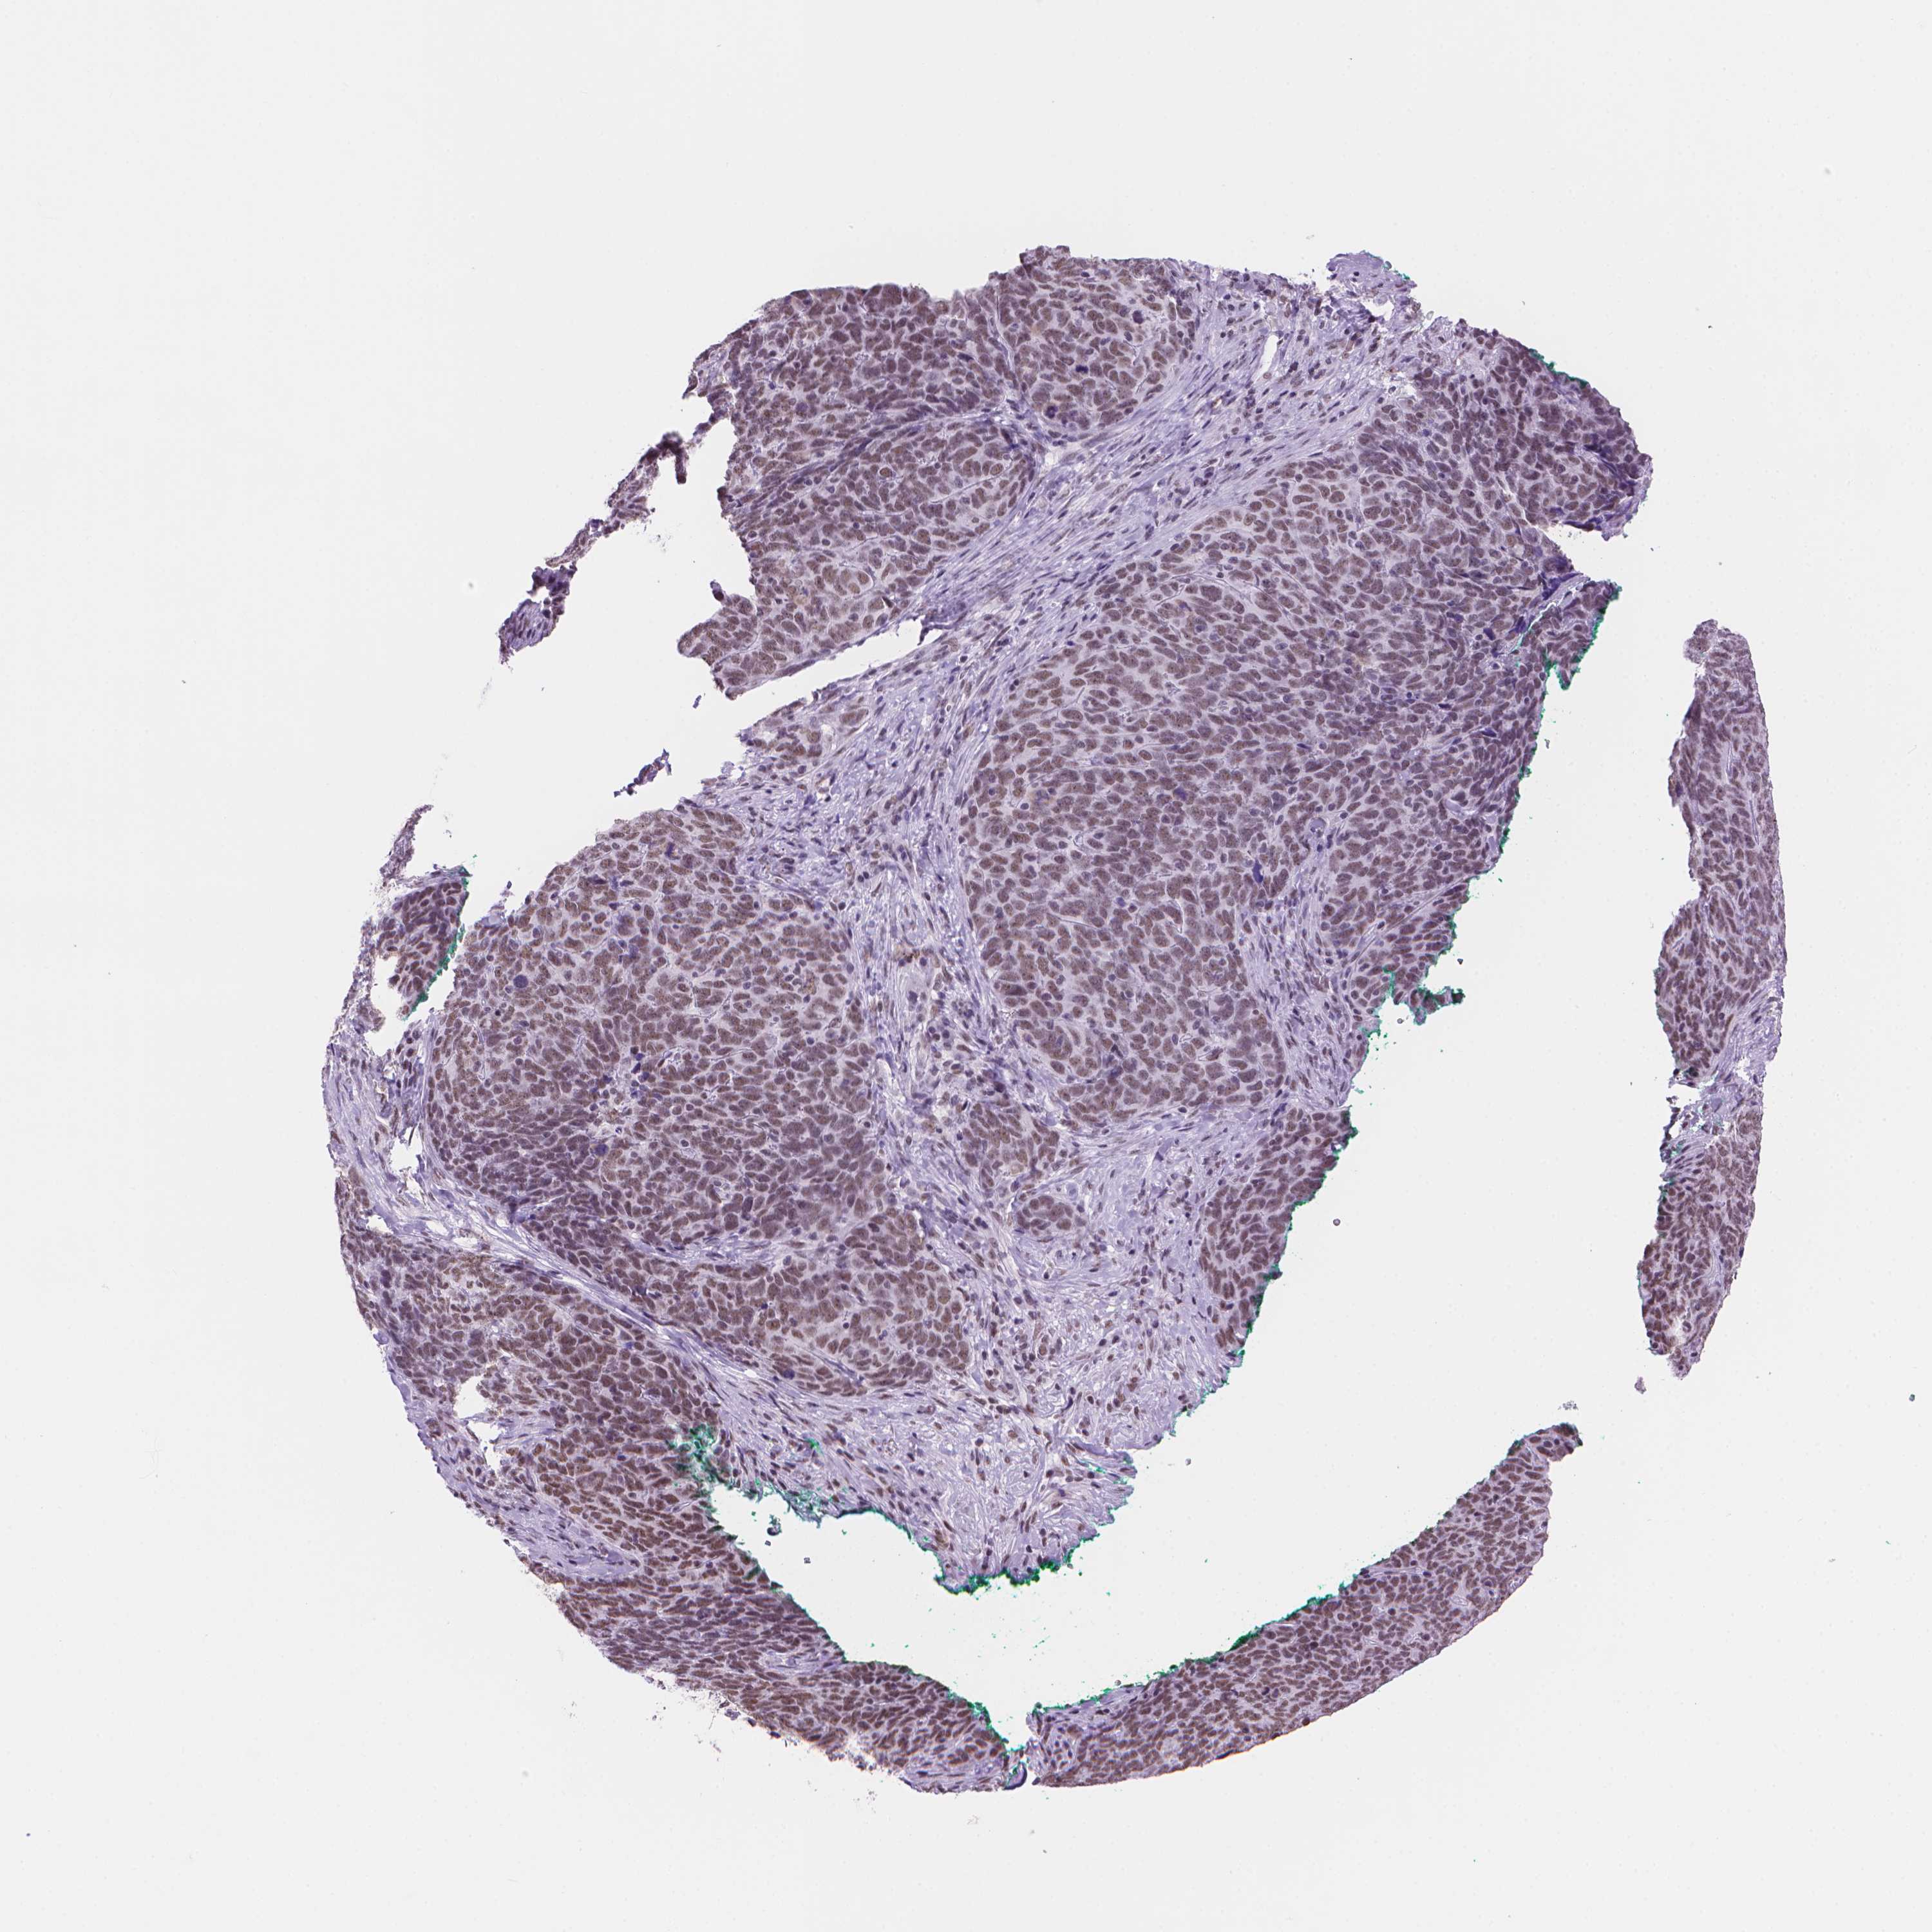

Basal cell and squamous cell cancer

SKIN CANCER - Protein expressioni

A mouse-over function shows sample information and annotation data. Click on an image to view it in a full screen mode. Samples can be filtered based on level of antibody staining by selecting one or several of the following categories: high, medium, low and not detected. The assay and annotation is described here.

Each image is clickable and will lead to virtual microscopy that enables deeper exploration of all samples and also displays staining intensity scores, fraction scores and subcellular localization as well as patient and tissue information for each sample.

Antibody HPA066010

Staining

High

Medium

Low

Not detected

Intensity

Strong

Moderate

Weak

Negative

Quantity

>75%

75%-25%

<25%

None

Location

Nuclear

Cytoplasmic/membranous

Cytoplasmic/membranous,nuclear

Basal cell carcinoma

Squamous cell carcinoma, NOS